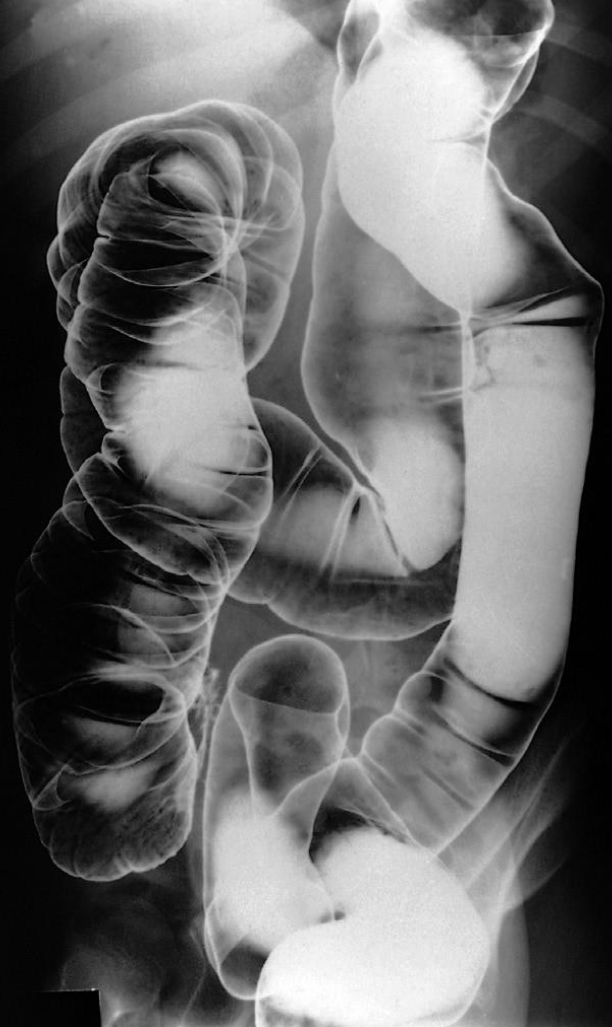

A. Give the name of the imaging examination in the given image. Enema double contrast

B. Give the NAMES of the used contrast media for the examination Barium & air (+ve Vs –ve)

Single & Double (rt) contrast barium enema

- The haustra are lost and the colon becomes narrowed and shortened, coming to resemble a rigid tube.

- Narrowing and shortening of colon Feature less colon give lead pipe appearances